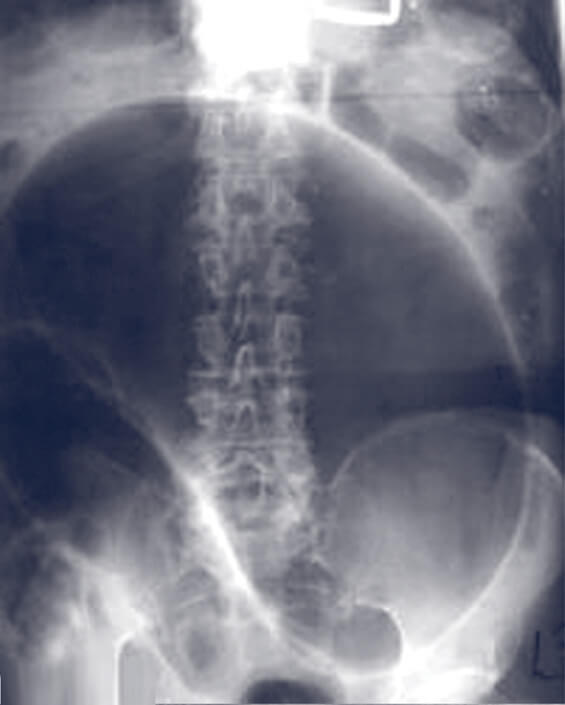

Making a diagnosis of a volvulus may be delayed in the elderly as the lack of bowel movements is presumed to be due to ongoing constipation. Younger patients may present with the more classic signs of an abdominal crisis, including severe abdominal pain and a rigid abdomen. In both groups, the abdomen is distended with an empty rectal vault. As the mesentery twists, the sigmoid colon comes to rest in the right upper quadrant, and the abdominal plain film shows what looks like a “bent inner tube” (figure 1). This finding may be seen in up to seventy five percent of cases. A barium enema showing a “bird’s beak” at the point where the two ends of colon become twisted, confirms the diagnosis in almost one hundred percent of cases. A colonic neoplasm is more common and must be considered as an alternative diagnosis.